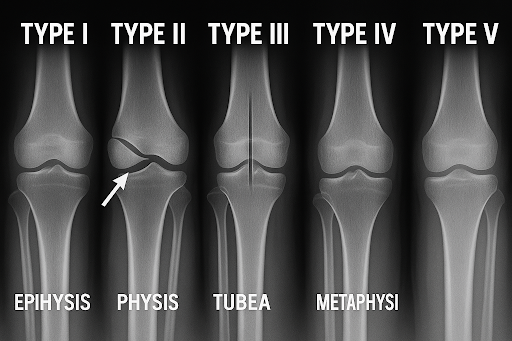

Salter-Harris fracture

Salter-Harris fractures are classified into five types based on the location and extent of the fracture:

- Type I: Separation of the epiphysis from the metaphysis through the growth plate

- Type II: Fracture extends from the growth plate into the metaphysis

- Type III: Fracture extends from the growth plate into the epiphysis

- Type IV: Fracture extends from the growth plate through both the epiphysis and metaphysis

- Type V: Crush injury of the growth plate